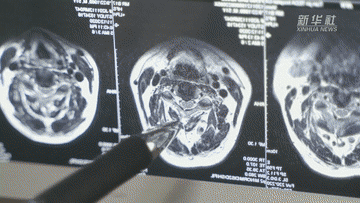

2012年,曹锋在侦办一起系列抢劫案中,因过度劳累从台阶跌落,右侧面部眼眶骨、颧骨等13处粉碎性骨折。就这样,曹锋肿着脸,忍着疼痛,一举破获了系列抢劫案件,却也因此落下了终身残疾。